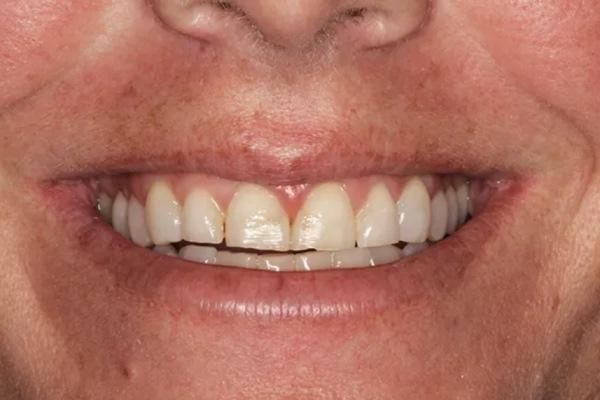

Для постоянной фиксации виниров использовался полупрозрачный цемент (RelyX Veneer Cement, 3M Oral Care) виниры были зафиксированы парами начиная с области центральных резцов, затем латеральные резцы и заканчивая клыками. Каждую реставрацию закрепляли с помощью 3-секундного светового отверждения, а излишки цемента удаляли с помощью ультразвукового скеллера. Окончательное отверждение осуществлялось путем полимерезации светом в течение дополнительных 20 секунд на каждый зуб. Результаты проведённого лечения показаны на фото с 9 по 12. Изменение улыбки пациентки с фиксированными постоянными реставрациями (фото 9). Демонстрация смыкания после лечения (фото 10). Портретная фотография анфас с широкой улыбкой (фото 11). Прицельные снимки зубов пациентки после проведенного лечения (фото 12).

Фото 11